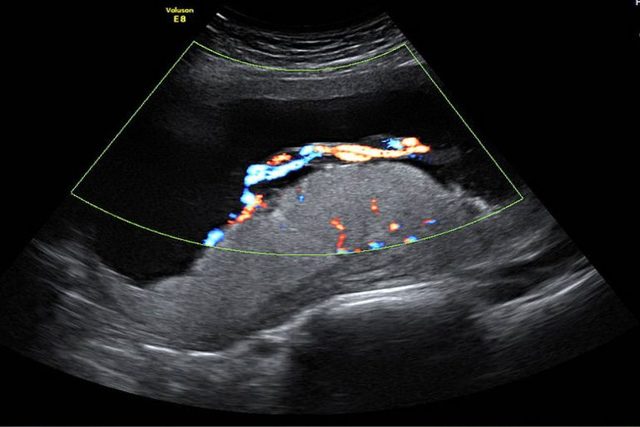

• ENEMIGO SILENCIOSO Y MORTAL

ENEMIGO SILENCIOSO Y MORTAL

La pre-eclampsia es una enfermedad que afecta el embarazo y que es la primera causa de mortalidad materna. Una vigilancia correcta evita complicaciones.

En las últimas 7 semanas del embarazo, además del crecimiento y desarrollo, se debe evaluar el BIENESTAR FETAL

• EVALUACIÓN INTEGRAL

EVALUACIÓN INTEGRAL

Es muy importante también, para corroborar el bienestar fetal, evaluar el volumen de líquido amniótico, la funcionalidad del cordón y la madurez placentaria; todo esto por Ultrasonido